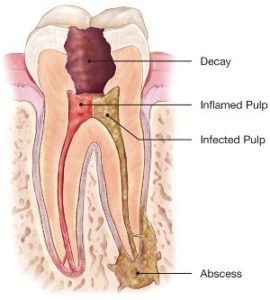

To understand endodontic treatment, it helps to know something about the anatomy of the tooth. Underneath the hard, translucent enamel and the less rigid, tubular structure called dentin, is soft-tissue called the pulp. The pulp contains blood vessels, nerves and connective tissue, from which both the dentin and the enamel are derived during early development.

The pulp spans the entire tooth, from the crown to the tip(apex) of the roots. Hence, inflammation, infection, and subsequent deterioration of the pulp can not only result in pain, but can also trigger breakdown of the surrounding bone and soft tissue (abscess), with which the pulp is in communication via an opening at the apex.

The most common reasons for inflammation or infection are deep cavities (caries), repeated dental procedures, cracks or fractures in a tooth.

Trauma, and even orthodontic movement (albeit very infrequently) can also cause inflammation and often shows up as discoloration of the tooth.